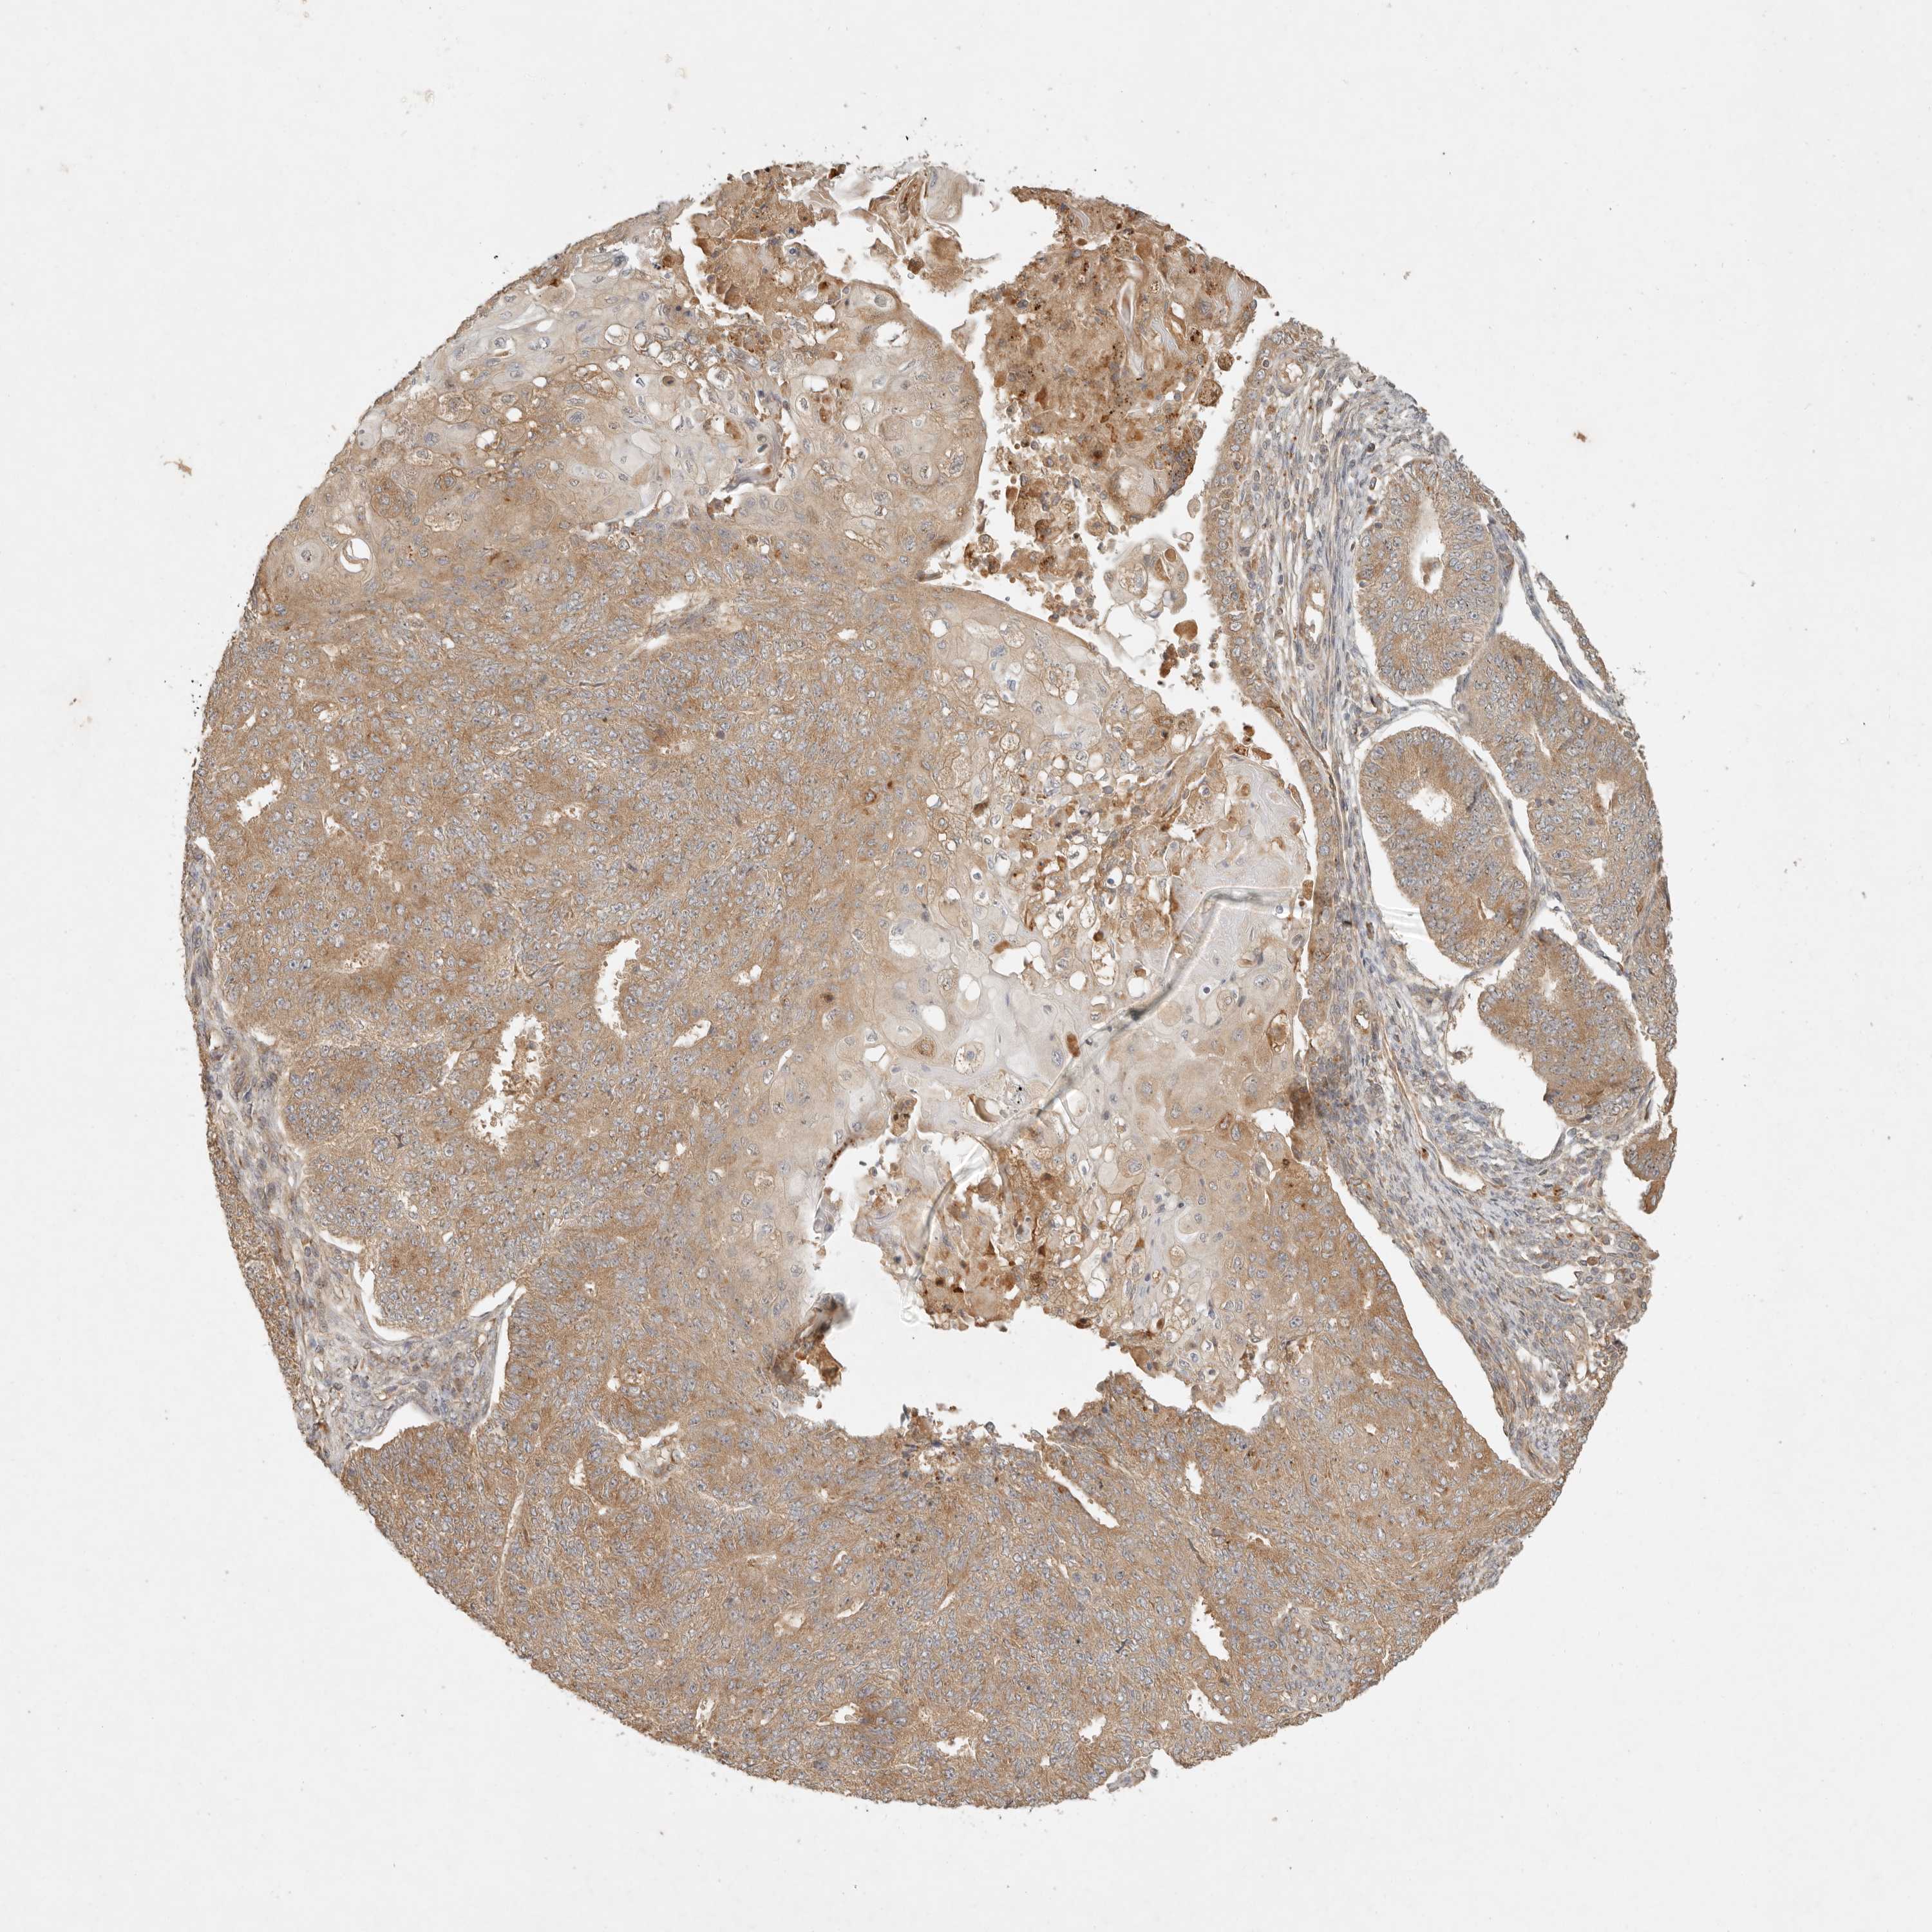

ENDOMETRIAL CANCER - Protein expressioni

A mouse-over function shows sample information and annotation data. Click on an image to view it in a full screen mode. Samples can be filtered based on level of antibody staining by selecting one or several of the following categories: high, medium, low and not detected. The assay and annotation is described here.

Note that samples used for immunohistochemistry by the Human Protein Atlas do not correspond to samples in the TCGA dataset.

Antibody stainingi

Antibody staining in the annotated cell types in the current human tissue is reported as not detected, low, medium, or high, based on conventional immunohistochemistry profiling in selected tissues. This score is based on the combination of the staining intensity and fraction of stained cells.

Each image is clickable and will lead to virtual microscopy that enables deeper exploration of all samples and also displays staining intensity scores, fraction scores and subcellular localization as well as patient and tissue information for each sample.

Antibody HPA029511

Staining

High

Medium

Low

Not detected

Intensity

Strong

Moderate

Weak

Negative

Quantity

>75%

75%-25%

<25%

None

Location

Nuclear

Cytoplasmic/membranous

Cytoplasmic/membranous,nuclear

Adenocarcinoma, NOS

Adenocarcinoma, metastatic, NOS